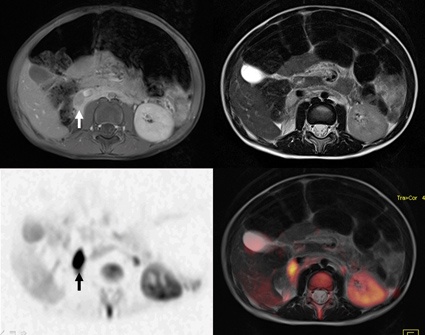

Das höchste Potential für eine moderne, individualisierte Diagnosefindung hat die MRT. Diese erlaubt neben der Erfassung morphologischer und funktioneller Aspekte den Einblick bis in molekulare Krankheitsprozesse. Einen hohen Stellenwert hat in den vergangenen 10 Jahren die MR-Ganzkörperbildgebung bei entzündlichen wie malignen Erkrankungen eingenommen. Ohne Umlagerung und in einem Untersuchungszeitpunkt kann mittels moderner MR-Geräte z. B. neben der Größe und Art des Primärtumors eine mögliche Ausbreitung bei Kindern bestimmt werden. Damit ist eine frühzeitige und hoch sensitive Krankheitserfassung möglich. Fehlt die spezielle neuroradiologische Expertise vor Ort, erfordert dies für die Kinderradiologie die zusätzliche Erfahrung im Bereich neuroradiologischer Aspekte.